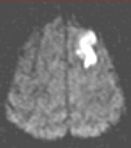

Routine FLAIR MRI images (left) cannot differentiate between acute infarcts and chronic ischemic changes/infarcts. The diffusion MRI (right) clearly demonstrates an acute infarct in the left frontoparietal region (the chronic changes do not "light up" on the diffusion study).